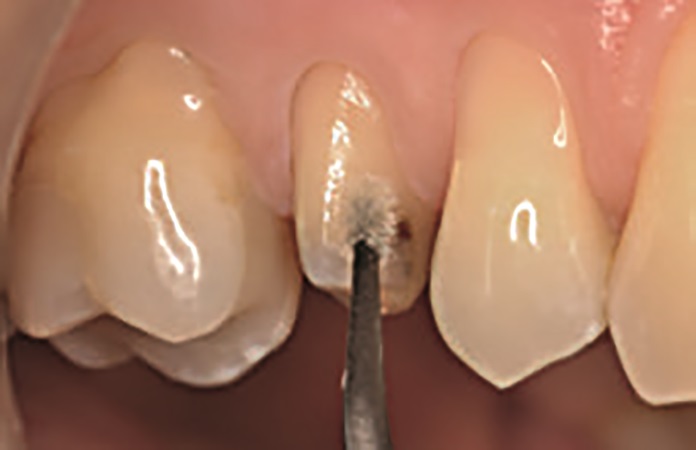

W przypadku odbudowy zęba 15 procedurę adhezyjną przeprowadzono z zastosowaniem protokołu wytrawiania self‑etch. Po dopasowaniu formówki Adapt SuperCap Matrix zaaplikowano OptiBond Universal zgodnie z wyżej opisanym protokołem — bez wcześniejszego zastosowania kwasu ortofosforowego (ryc. 12). Odstąpiono od użycia wkładów koronowo‑korzeniowych w tym przypadku. Wykonany dostęp endodontyczny umożliwił uzyskanie optymalnej retencji, a dzięki kształtowi zachowanych tkanek i długości korony zęba 15 osiągnięto rozległy efekt obręczy. Odbudowa została wykonana przy użyciu systemu SonicFill™2 – kompozytu bulk‑fill z końcówką dźwiękową do aktywacji materiału. SonicFill to kompozyt o wysokiej zawartości cząstek wypełniacza, zawierający opatentowaną żywicę ze specjalnymi modyfikatorami, reagującymi na energię dźwiękową. Na skutek aplikacji energii dźwiękowej i działania modyfikatora dochodzi do spadku lepkości i zwiększenia płynność materiału. Umożliwia to optymalne umieszczenie i dopasowanie wypełnienia do ścian ubytku. Po zaprzestaniu działania energii dźwiękowej kompozyt ponownie staje się bardziej lepki i zwarty, co sprzyja efektywnemu modelowaniu wypełnienia. Kompozyt ten cechuje się także optymalnym skurczem polimeryzacyjnym pozwalającym na wyższe stężenie inicjatorów sprzyjających bardziej efektywnemu procesowi polimeryzacji. Ponadto dzięki dopasowaniu współczynnika załamania światła i wydajnym mechanizmom utwardzania SonicFill2 jest możliwa jego polimeryzacja na maksymalnej głębokości wynoszącej 5mm. W związku z tym przed rozpoczęciem procedury zmierzono głębokość ubytku sondą, aby upewnić się, że grubość planowanej warstwy kompozytu będzie odpowiadała maksymalnej głębokości polimeryzacji tego materiału. Następnie wykonano odbudowę ubytku za pomocą jednej warstwy SonicFill2 (ryc. 13), który został spolimeryzowany za pomocą lampy Demi Ultra Light (ryc. 14). Po zakończeniu polimeryzacji usunięto formówkę, a wypełnienia w zębach 16 i 14 wykończono i wypolerowano za pomocą kolejnych krążków OptiDisc™ o coraz drobniejszym nasypie, a następnie jednoetapowego systemu Opti‑1Step™ (Kerr). Wygładzanie i polerowanie odgrywa istotną rolę w sposobie interakcji światła z uzupełnieniem. Mały, jednolity rozmiar cząsteczek materiału nanohybrydowego Harmonize™ został zaprojektowany w celu uzyskania optymalnej polerowalności.